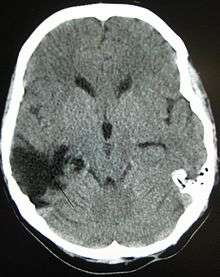

A contusion could be caused by direct damage to the head, where a bruise is bleeding on the brain.

A coup-contrecoup injury occurs when the force impacting the head is not only strong enough to cause a contusion at the site of impact, but also able to move the brain and cause it to slam into the opposite side of the skull, which causes the additional contusion.